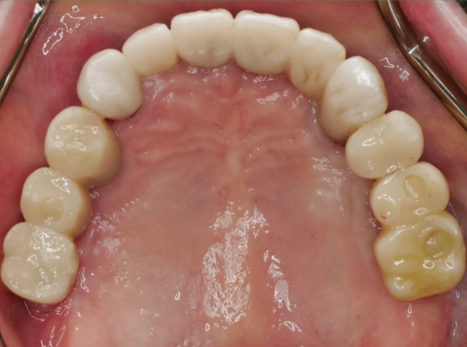

為了徹底解決問題,讓廖阿姨重拾咀嚼能力和生活品質,我們為她規劃了完善的治療方案:植入6顆人工植體作為堅固的「地基」,再裝上全新的固定式假牙(全口固定假牙重建)。

🌟 治療後,廖阿姨收穫了雙重驚喜:

1️⃣ 「食」力全開! 穩固的固定假牙讓廖阿姨終於能重新享受各種美食,吃得香、營養足,身體自然更健康!

2️⃣ 意外變「順」眼! 除了恢復咀嚼功能,更讓廖阿姨驚喜的是,原本因缺牙和牙橋造成的輕微「凸嘴」外觀,竟然也一併改善了!臉型線條變得更柔和、更自然,笑容也更加自信迷人!😄

3. 高效重建: 結合原有的兩顆植體與新植入的四顆植體,共計六顆植體作為支撐基礎。利用特殊的連接裝置(如桿柱或橋接設計),為林先生鎖上一組穩固的全口固定式假牙(All-on-6 hybrid prosthesis)